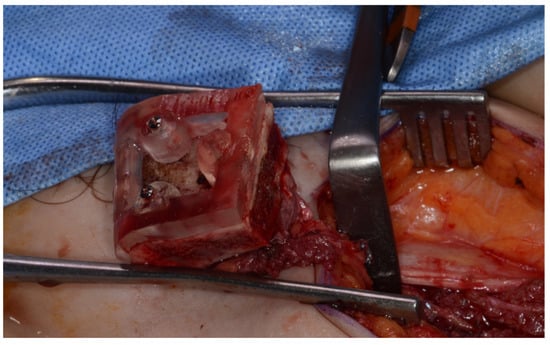

Surgery was performed under general anesthesia. #45, 46, and 47 were extracted. Segmental mandibulectomy was performed using a surgical guide through a submandibular approach. (Figure 6). The left iliac crestal DCIA flap was harvested according to the surgical guide. (Figure 7) To minimize the morbidity of the donor site, the donor site was reconstructed using titanium mesh and allobone chip graft. (Figure 8) Microvascular anastomosis was performed using the facial artery and facial vein. Fixation of the resected mandible and the bicortical iliac bone flap was achieved using a customized reconstruction plate (Cusmedi ©, Sungnam, Republic of Korea) designed to have a thickness of 2 to 3 mm according to the patient’s mandibular morphology and the periphery of the iliac bone flap and 3D printed by the selective laser melting (SLM) method and eight 2.3 mm reconstruction screws. (Figure 9). A silastic drain was inserted into the submandibular region and sutured. (Figure 10) The final diagnosis was ameloblastoma.

Figure 6.

Surgical guide for segmental mandibulectomy.

Figure 7.

Harvested DCIA iliac crestal bone and internal oblique muscle flap with an iliac guide.